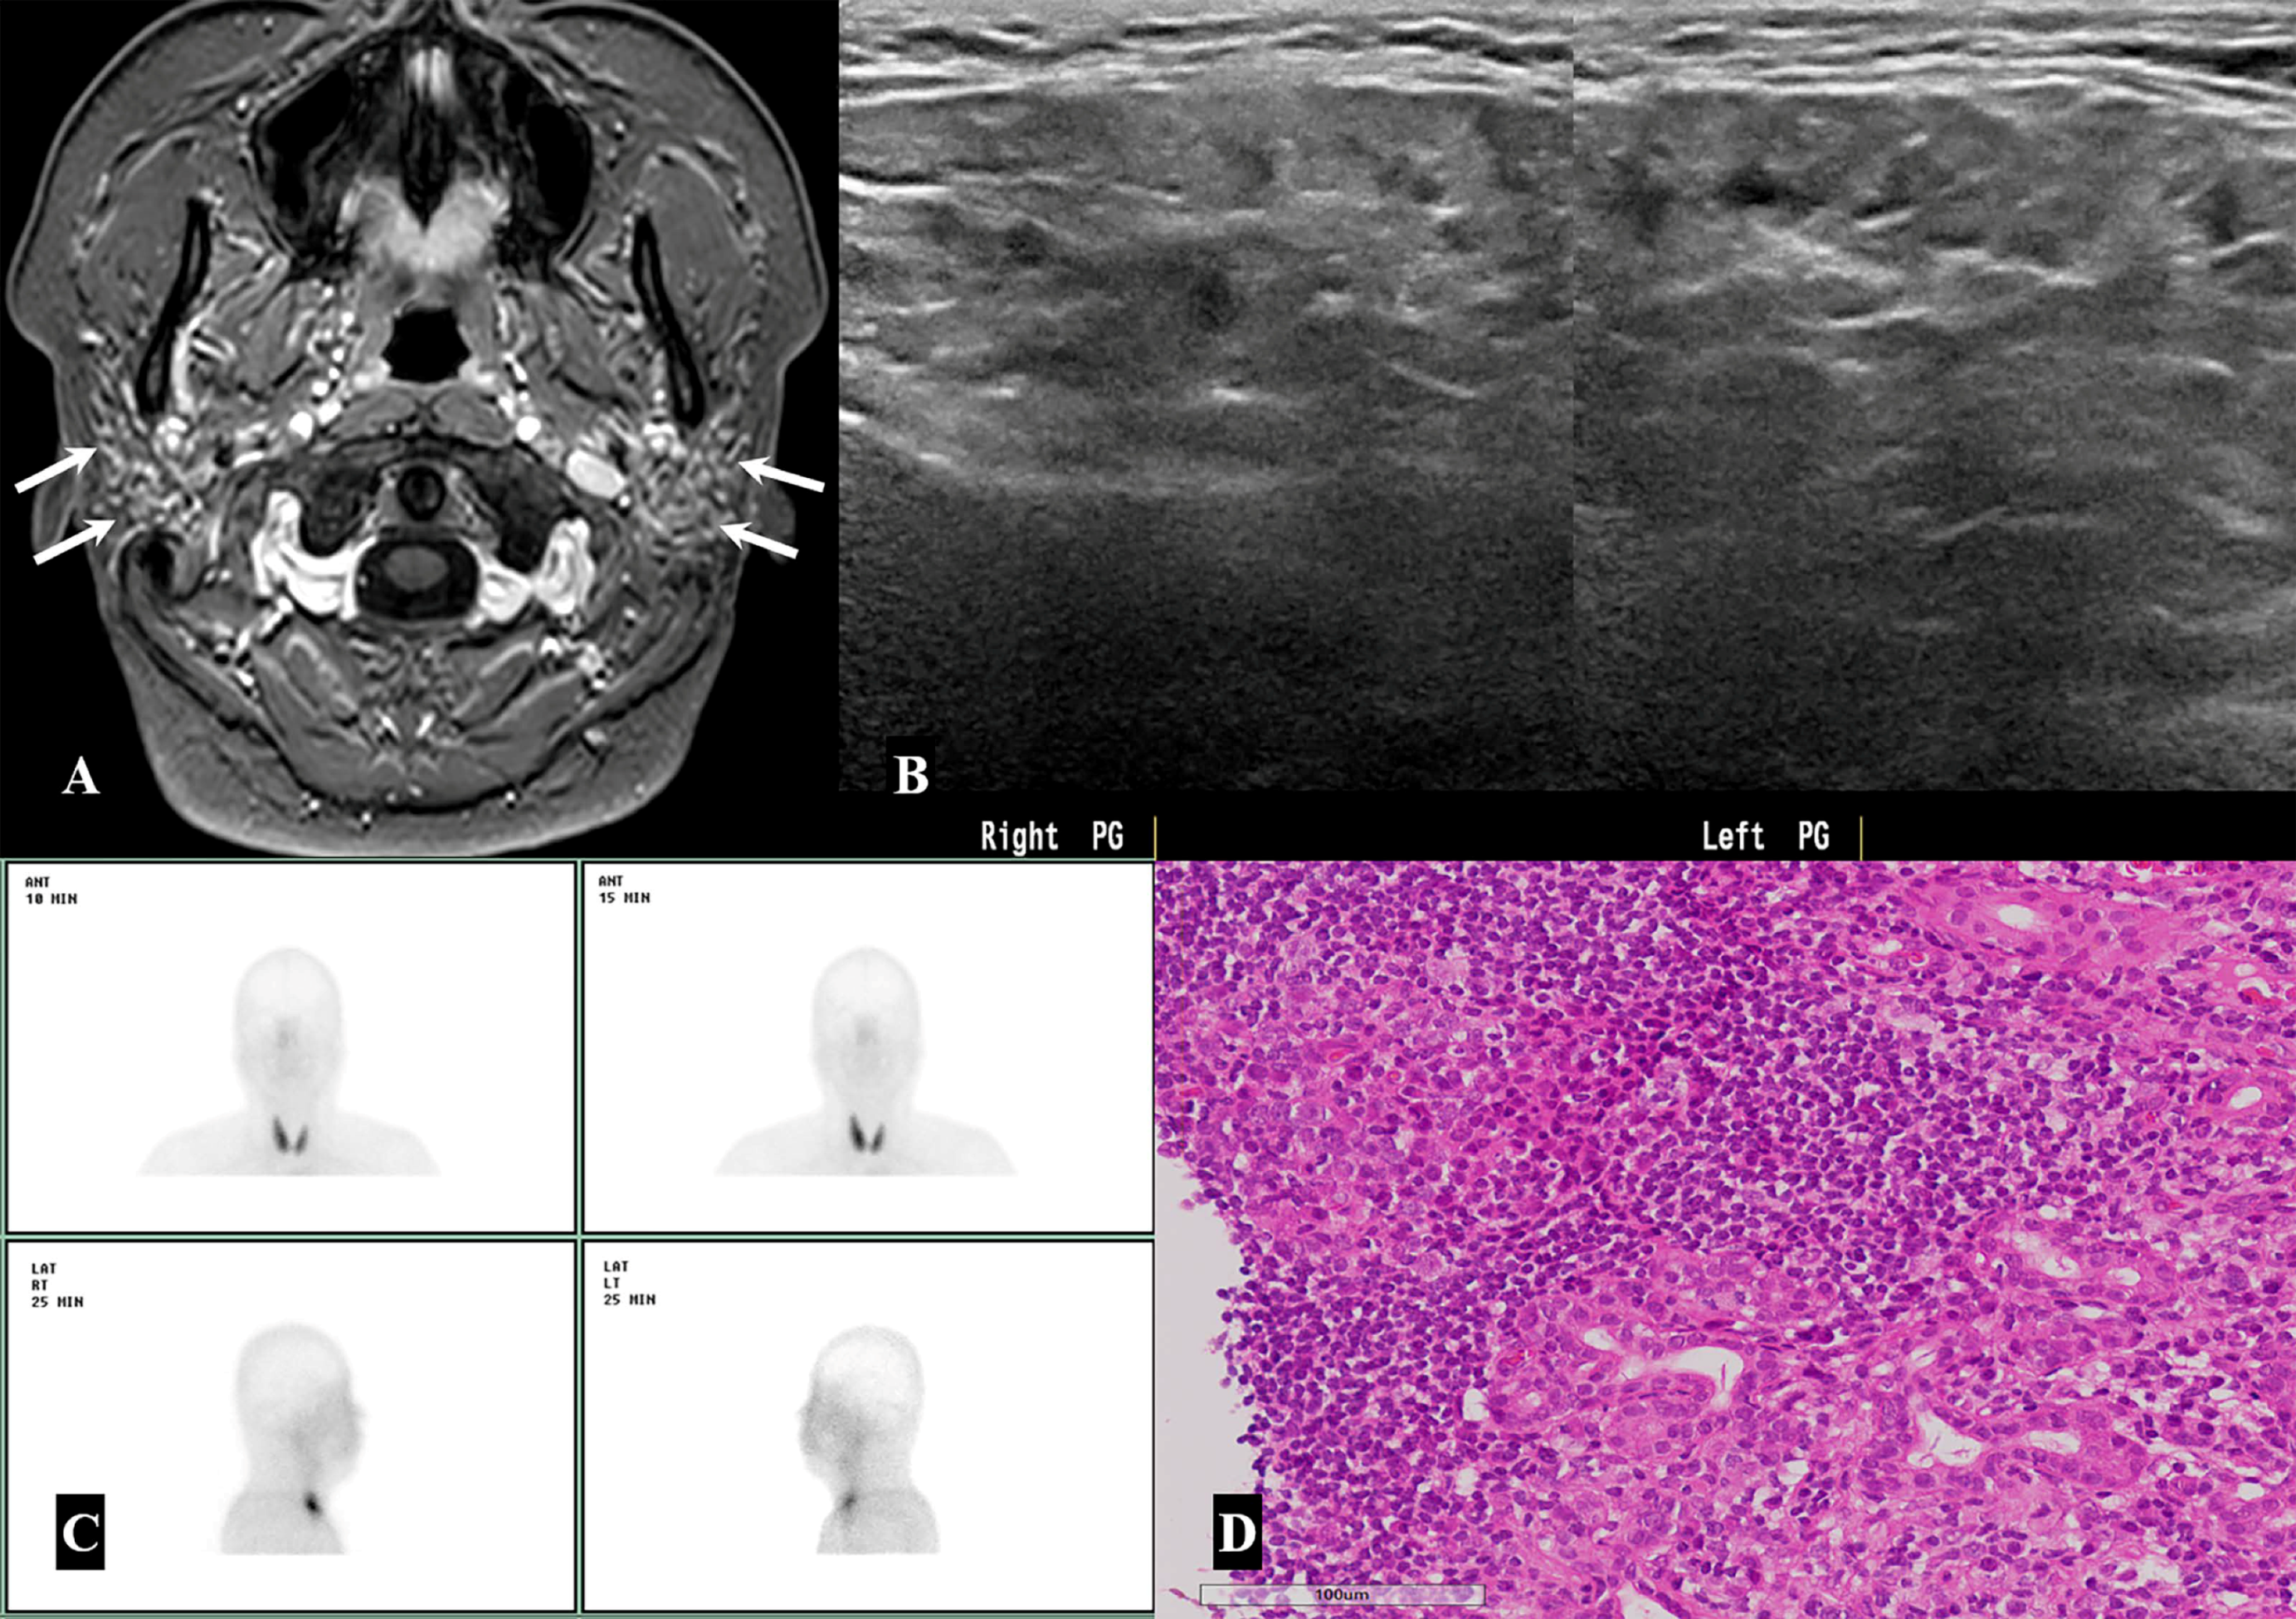

| Sjögren’s syndrome | 6/49 (12.3%) |